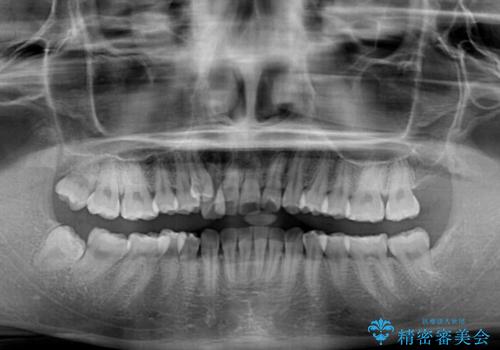

- 八重歯と、それによる正中のズレを気にして来院された患者様です。

口元の突出感は気にしていなかったため、上顎の左右第一小臼歯を抜歯することで、八重歯の解消と上顎の正中を改善していくこととしました。

奥歯の咬み合わせを維持しながら正中位置を改善するために、補助装置を使用しました。

予定より期間がかかりましたが、上下の正中位置を綺麗に一致させることができました。